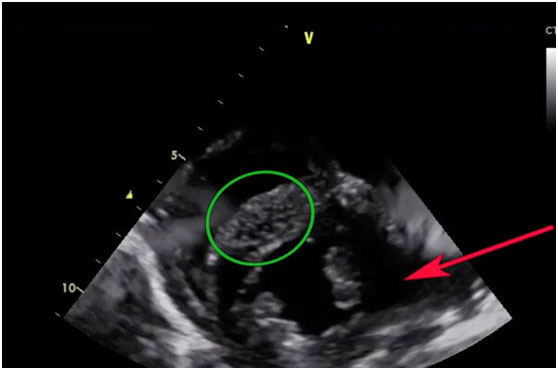

Drexel的研究人員利用心臟的電活動來激活超聲波成像示蹤劑,讓醫(yī)生更好地觀察心臟肌肉中的血液流動--這可以讓醫(yī)生發(fā)現(xiàn)心臟病的早期跡象。在這張使用示蹤劑Electrast的超聲波圖像中,綠色圓圈區(qū)域正在接受血液,而紅色箭頭所指的區(qū)域則沒有。